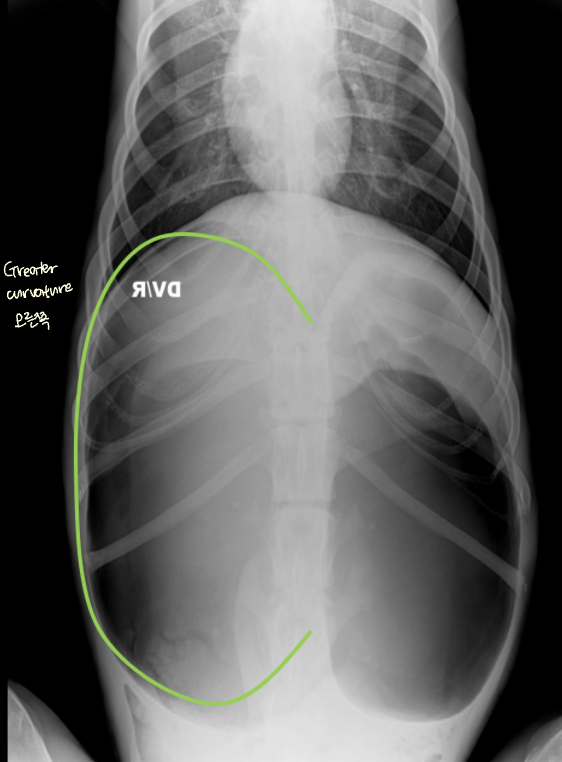

| GD | GDV | |

| VD | - greater curvature ์ผ์ชฝ(์ ์) * 360๋ ํ์ ์์๋ ์ผ์ชฝ์ ์์น | - greater curvature ์ค๋ฅธ์ชฝ (180๋ ์ผ์ ) - duodenum ์์น๋ ํจ๊ป ๊ผฌ์ |

| RL | - pylorus๊ฐ ์๋์ชฝ(์ ์) | - pylorus ์์ชฝ - ์์ ๋ถํํ(compartmentalization) : ๋ถ๋ฐฉ ํ์ธ - gastric band (soft tissue) ๊ด์ฐฐ |

![]() ![]() | ![]() ![]() | |